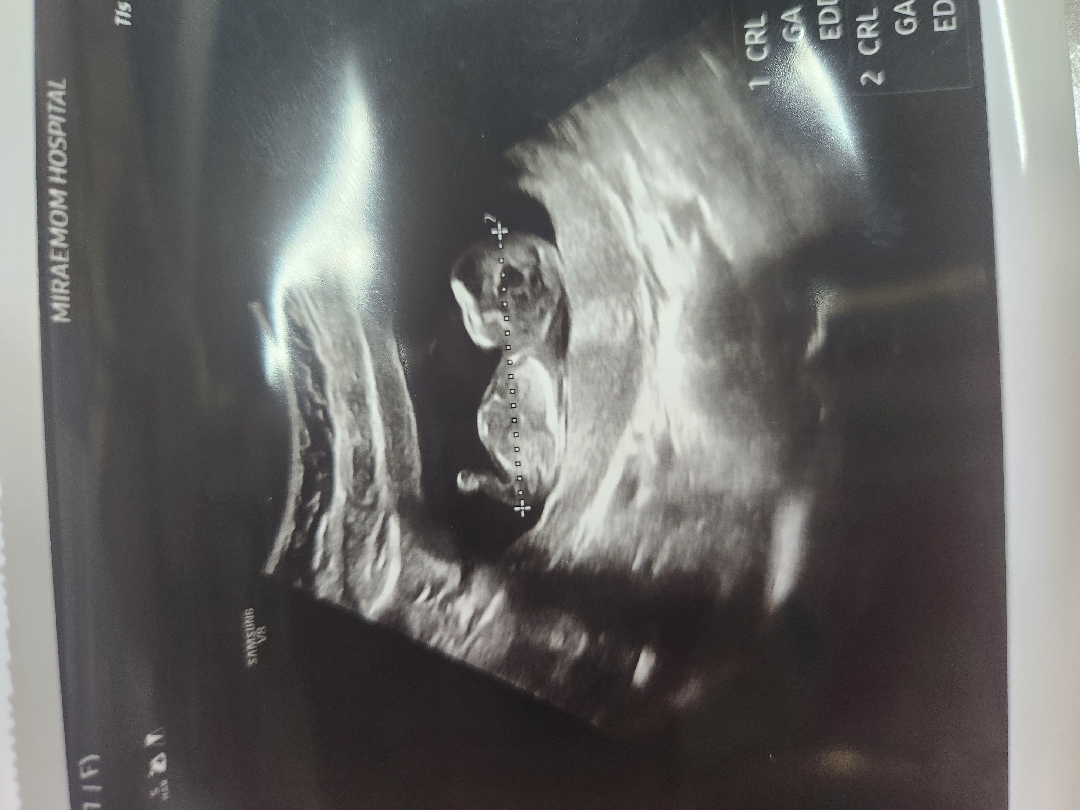

12주3일차 각도법 볼수있나요?

딸만 둘인데 늦둥이 셋째 아들인지 딸인지 각도법 봐주실수있을까요?